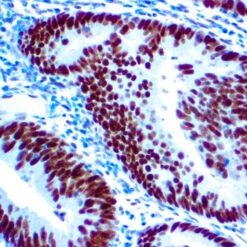

This antibody reacts with a 33-36 kDa protein known as ERCC1 (excision repair cross complementing) polypeptide. ERCC1 is required for nucleotide excision repair of damaged DNA and is homologous to RAD10. In mammalian cells, XPG cleaves 3’ of the DNA lesion while ERCC1-XPF complex makes the 5’ incision.

| Cellular Localization | Nuclear |

| Positive Control Tissue | Tonsil |